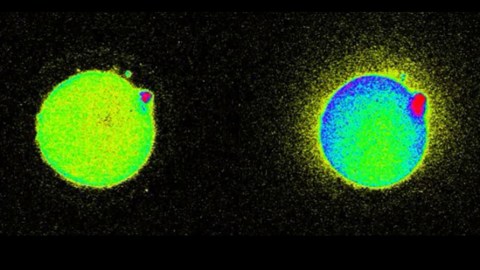

Image source: Northwestern

The team injected an egg with sperm enzyme. (The use of actual sperm in experiments is illegal.) Doing this triggers an increase in calcium within the egg that then causes zinc to be released. The zinc binds to small molecule probes, that emit light that can be seen under a fluorescence microscope as a spark. From there, millions of zinc molecules explode momentarily all around the outside of the egg.

Being able to observe all this, and non-invasively, is important because zinc is critical for the development of a healthy embryo, and Northwestern has previously established that zinc is actually what triggers an embryo to grow and change into a distinct new organism, that is, a new person.